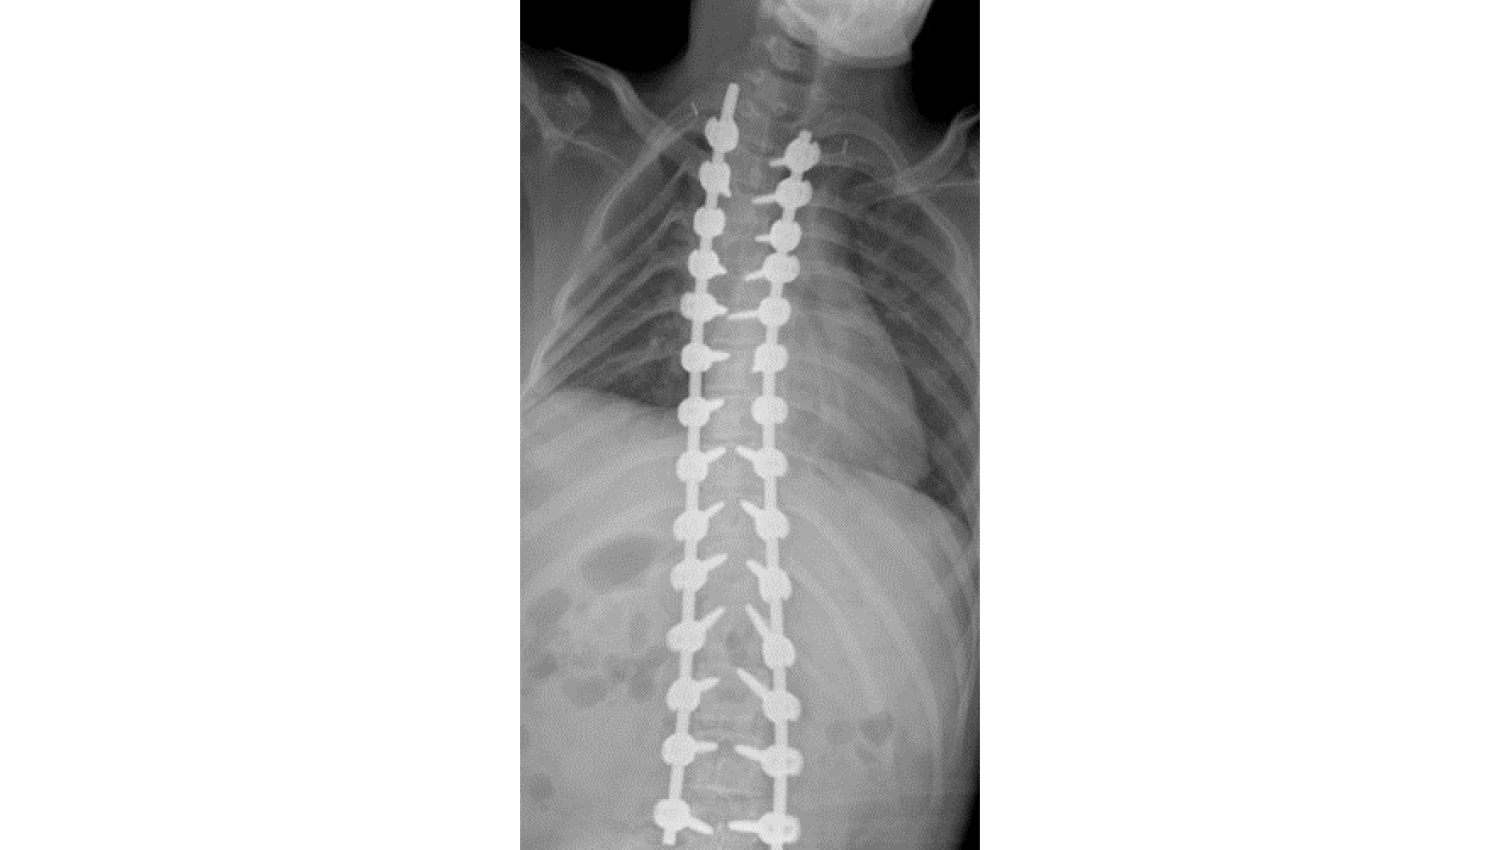

• Metrosan-Ligamed Posterior Polyaxial Spine Stabilization Screw 5,5x35/ 5,5x40/ 5,5x45 -Metrosan-Ligamed Polyaxial reduction screw 5,5x35/ 5,5x40/ 4,5x30/ 4,5x25 -Metrosan-Ligamed Titanium Rod 55x450mm -Powerbone Flexible Graft were used for the patient with scoliosis due to cerebral palsy disease.

2.Metrosan-Ligamed Posterior Polyaxial Spine Stabilization Screws, Titania Polyaxial Reduction Screw, Titanium Rod and Powerbone Flexible Greft products were used with surgical intervention to treat scoliosis.